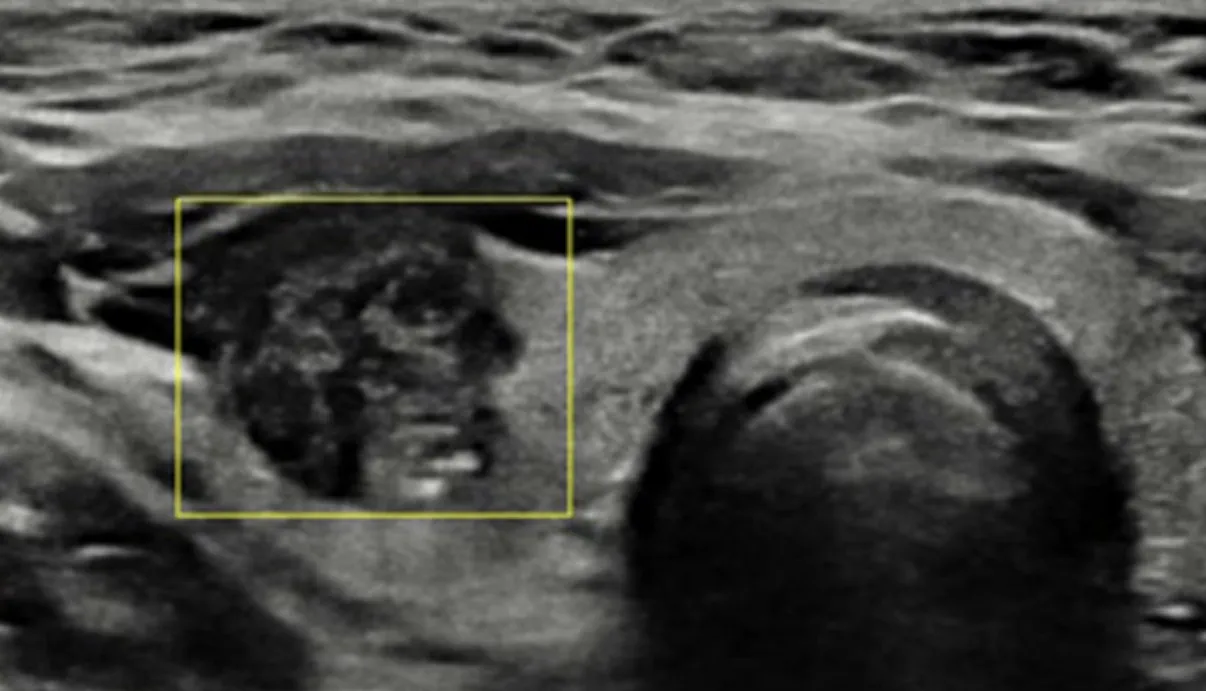

땡큐서울의원_갑상선결절 초음파 이미지

갑상선 일부가 국소적으로 커지며 생기는 덩어리를 갑상선 결절이라 하며, 전체 인구의 약 5%에서 발견될 만큼 흔한 상태입니다. 대부분은 양성이고 악성(암)으로 확인되는 경우는 전체 결절의 5% 안팎에 불과하지만, 발견 시 악성 여부를 먼저 확인하는 것이 중요합니다. 양성으로 판단되면 갑상선 기능은 대개 정상적으로 유지되며, 결절이 매우 커져 주변 조직을 압박하지 않는 한 건강에 직접적인 위협이 되지는 않습니다.

갑상선결절의 90~95% 이상이 양성으로, 갑상선 결절 환자의 대부분은 이 범주에 해당합니다. 양성결절은 주변 조직을 침범하거나 다른 부위로 전이될 가능성이 없으며, 갑상선 기능도 대부분 정상적으로 유지됩니다. 결절이 매우 커져 식도나 기도를 압박하거나 외형적으로 문제가 되지 않는 이상, 생명에 직접적인 영향을 주지 않으므로 과도하게 걱정할 필요는 없지만 정기적인 추적 관찰을 통해 확인하는 것이 권장됩니다.

악성결절 (갑상선암)

초기에는 증상이 거의 없어 발견이 늦어지는 경우가 많습니다. 진행되면 주변 조직과 장기를 침범하고, 목 림프절이나 폐·뼈 등 원격 부위로 전이될 수 있으며, 이 경우 생명에 영향을 줄 수 있어 적극적인 치료가 필요합니다. 다만 갑상선암의 대부분을 차지하는 유두암과 여포암은 예후가 좋아 조기에 발견하면 완치율이 매우 높습니다. 따라서 세포검사를 통해 악성 여부를 정확히 확인하고, 전문의와 충분히 상담하여 치료 방침을 결정하는 것이 중요합니다.